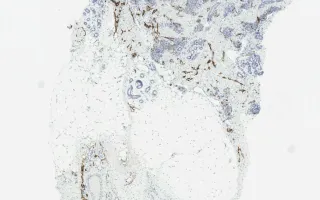

Blood vessels, tufted hemangioma, D2-40 stain

Tufted hemangioma

13 month old male infant with a tumour on the shoulder.

Tufted angiomas are benign vascular lesions which often occur on the neck or shoulders of children or young adults. Microscopically, they are comprised of nodules of tightly packed capillaries which may involve the dermis and superficial subcutis. Crescentic cleft-like vessels or semilunar lymphatic channels are generally seen at the periphery of some of the capillary tufts (nodules). These vessels are lined by unremarkable endothelial cells (CD31 positive) and surrounded by pericytes (smooth muscle actin positive). D2-40, a marker of lymphatic endothelial cells, is expressed in the crescentic cleft like vessels, but the proliferative capillaries are negative. The capillary lumina are not readily evident in many areas. GLUT-1 was negative in this case; it is positive in juvenile hemangiomas.

This slide shows D2-40 stain, see Related Content for H&E, CD31, and SMA stains.